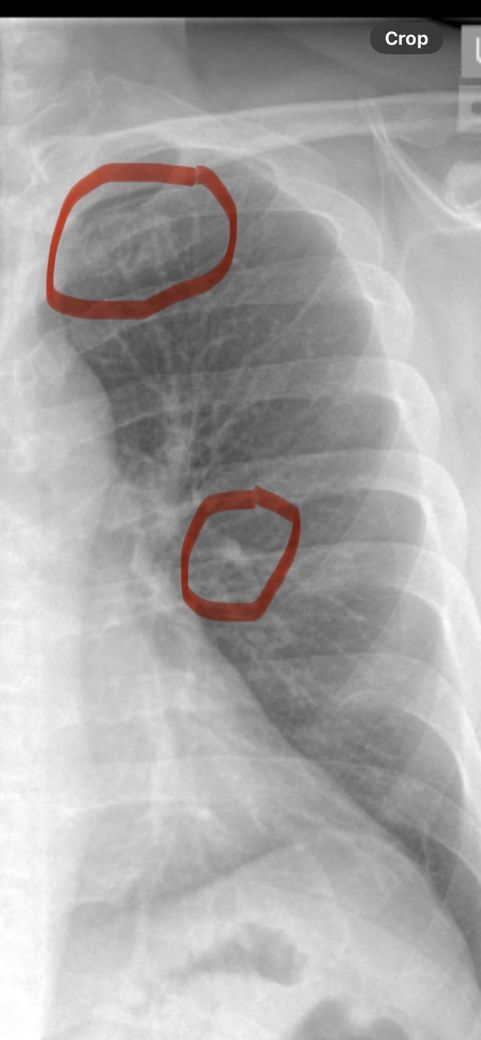

미국에서 흉부 통증으로 urgent care 방문후 엑 스레이 촬영했는데 사진 확인부탁드립니다

명치주변 그리고 위쪽으로 쥐는듯한 통증이 있어서 폐암이 무서워서 급한대로 urgent care에서 흉부 엑스레이 촬영 및 피검사를 했고 문제가 없다고 하는데.... 어전트케어에는 보통 수간호사가 의사 역활을 해서 사진에 이상이 있는지 확인하 고 싶습니다. 오른쪽 위 쇄골쪽 동그란 형태? 그리고 중앙에 하얀색으로 점처럼 보이는게 괜찮은건가요?... ct 촬영을 하 려면 반년을 기다려해서 걱정입니다

• 1번 째 사진

X-ray에 표시해주신건 1번 갈비뼈와 기관지입니다. 문제 없는 모습이니 걱정 안하셔도 되겠습니다.